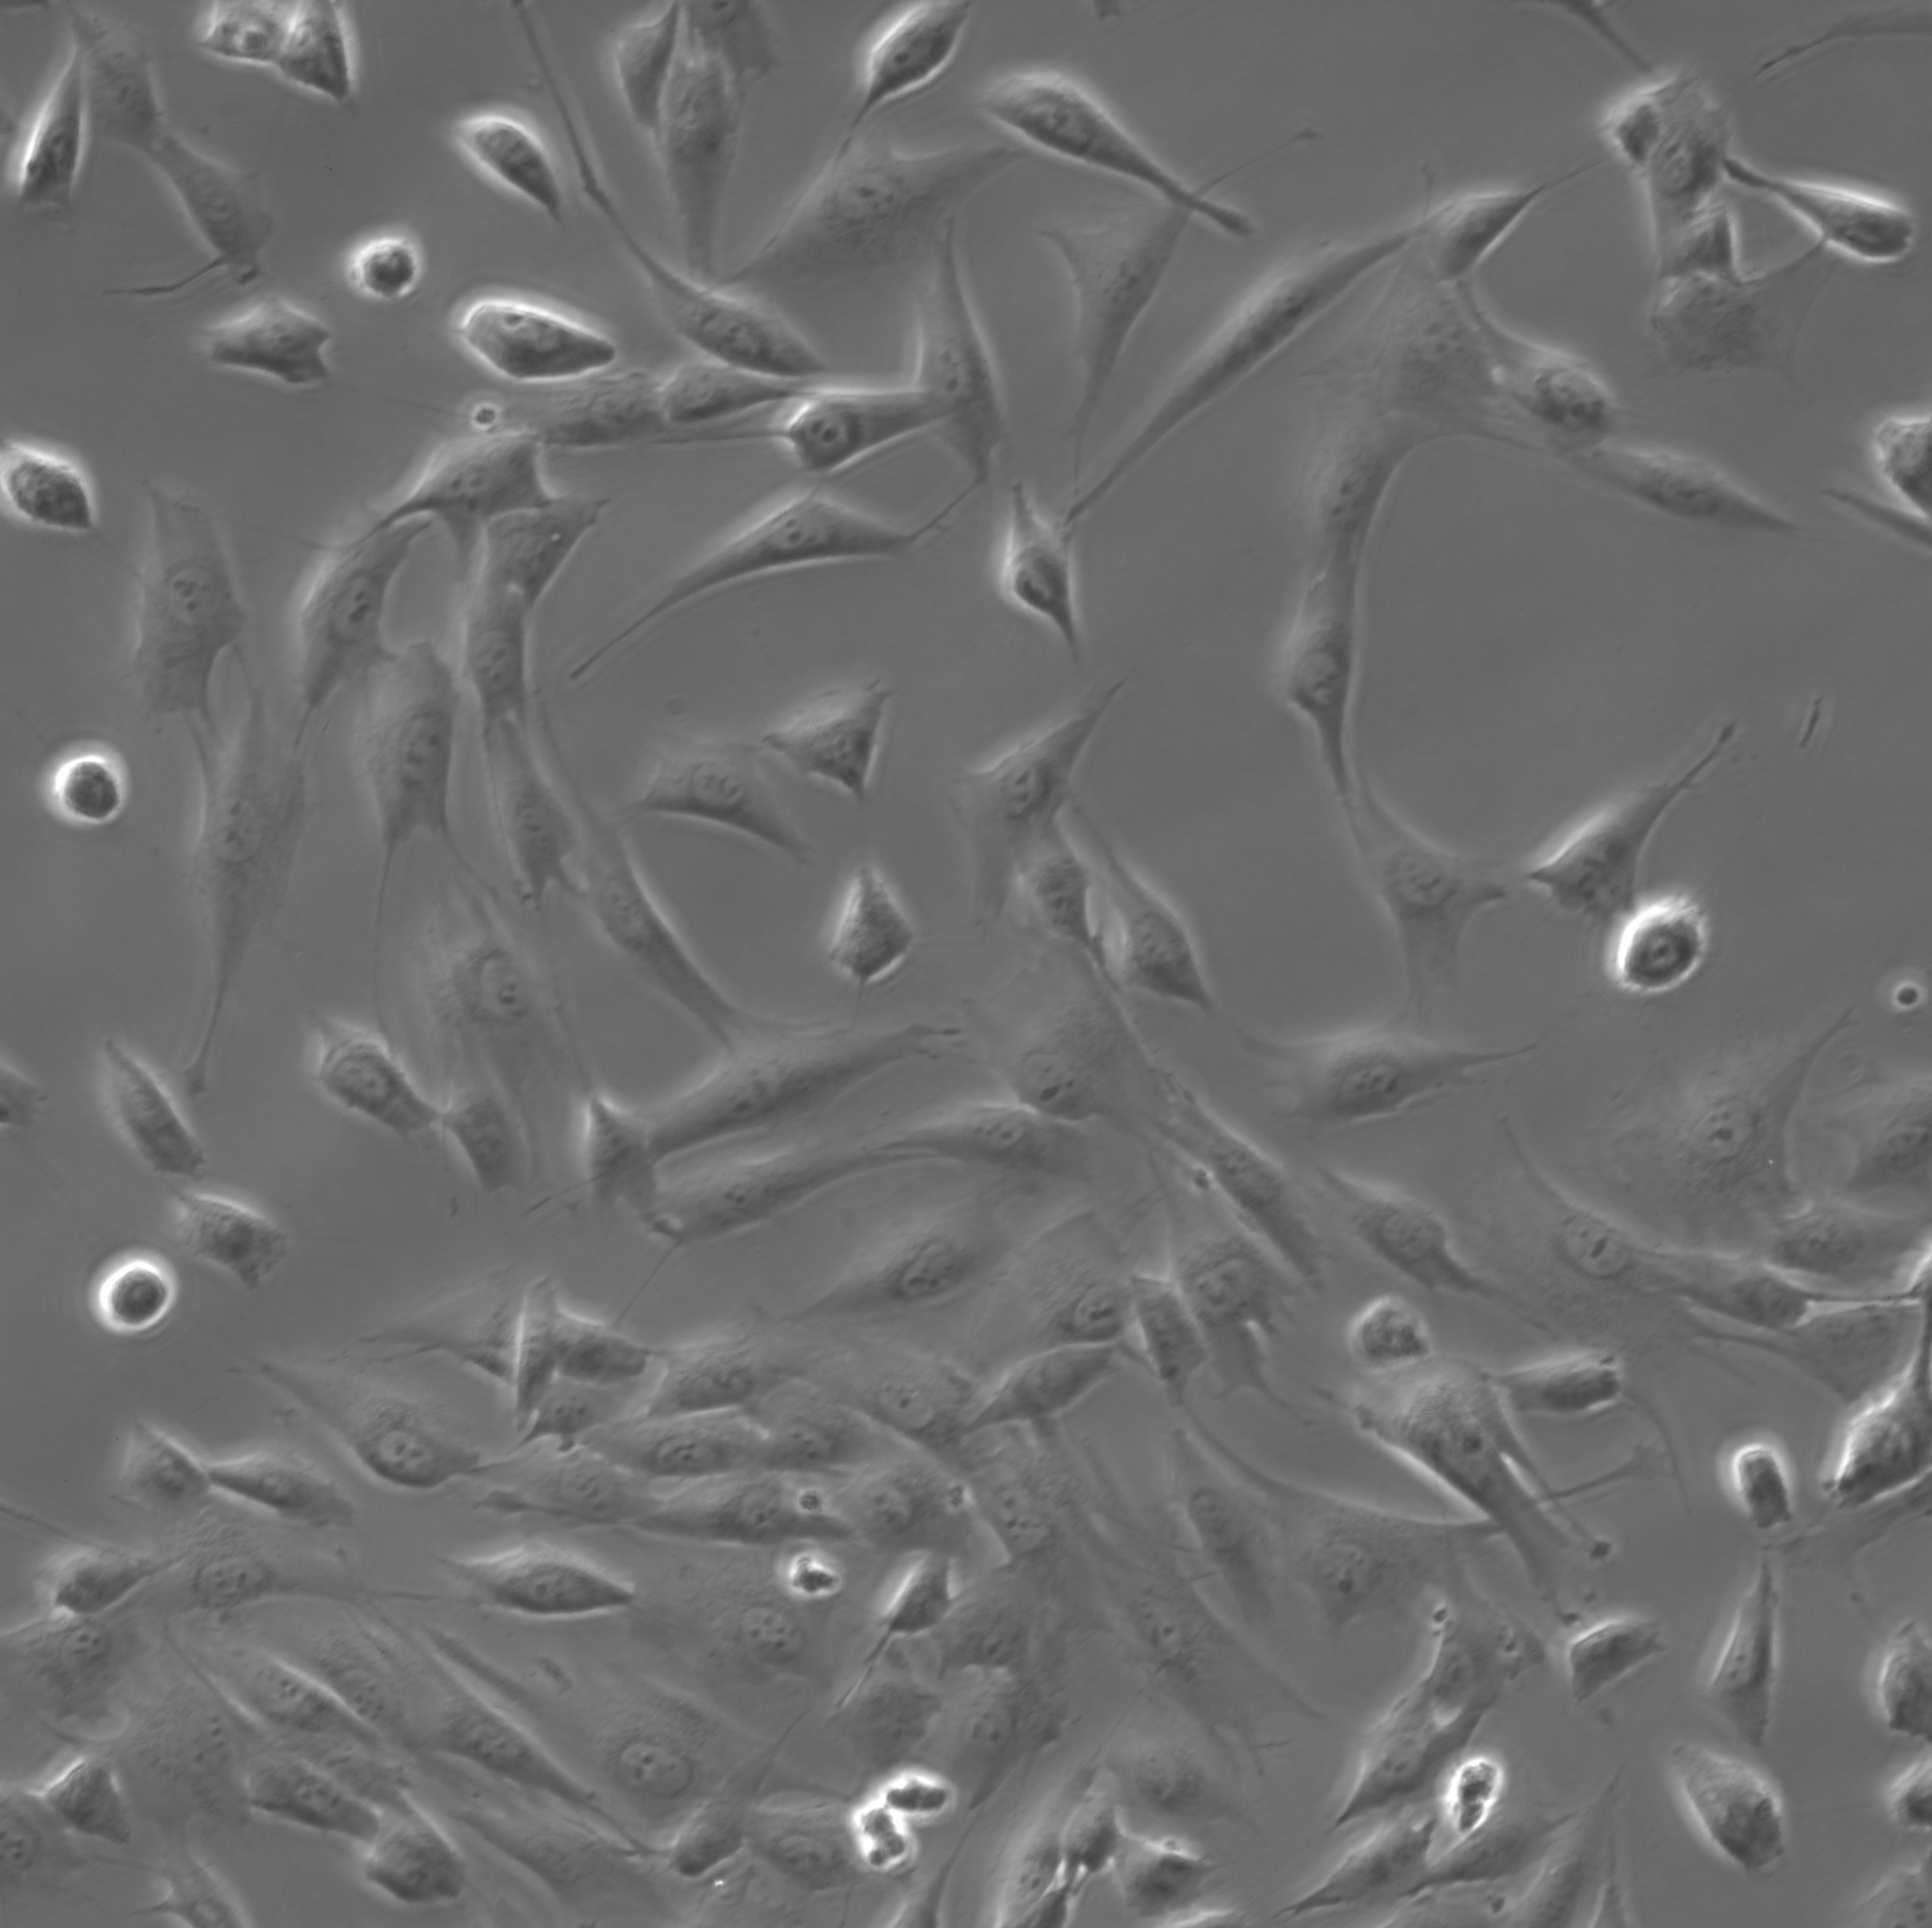

MG-63 osteosarcoma cells, phase-contrast 20×

MG-63 osteosarcoma cells, phase-contrast 20×